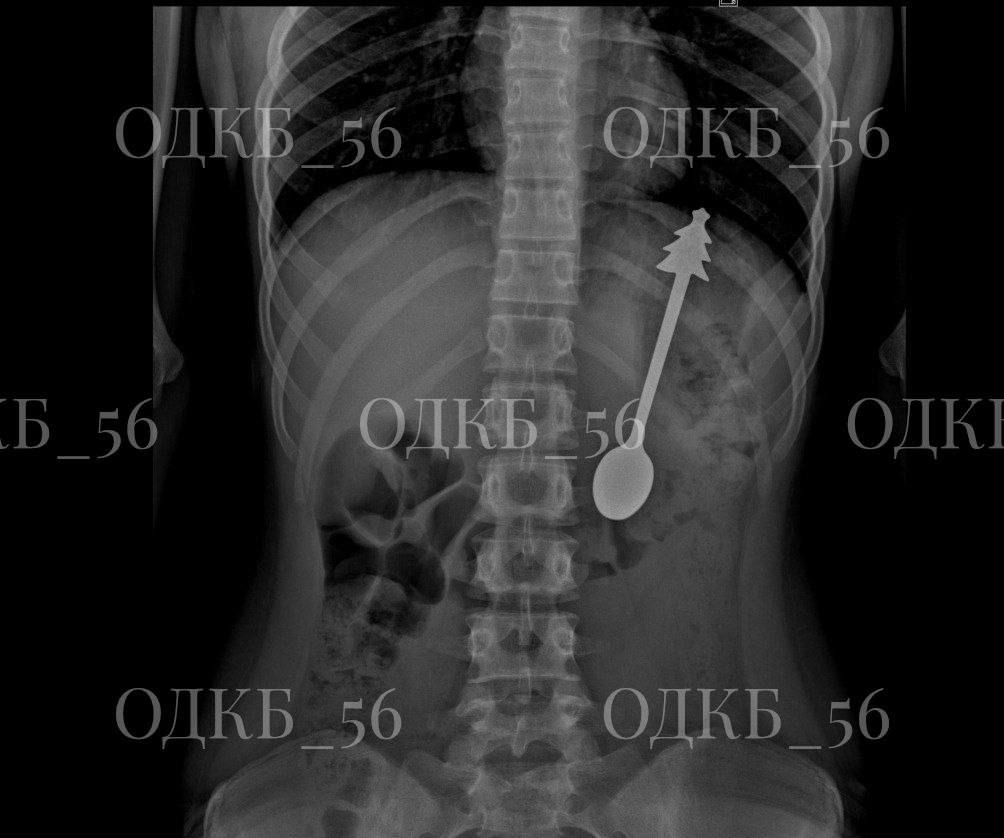

По прибытии в больницу, ребенка осмотрели дежурные врачи и направили на рентгенографию брюшной полости. Снимки подтвердили опасения – в желудке отчетливо визуализировалась ложка, длина которой составляла 14 сантиметров. Это представляло серьезную угрозу для здоровья ребенка, так как инородный предмет мог вызвать травму слизистой оболочки желудка, перфорацию (прободение) стенки желудка или даже миграцию ложки в другие отделы пищеварительного тракта. Кроме того, длительное нахождение предмета в желудке могло спровоцировать воспалительные процессы и развитие осложнений.

Врачи детского хирургического отделения, оценив ситуацию, приняли решение о проведении экстренной эндоскопической операции. Этот метод является малоинвазивным и позволяет извлечь инородный предмет, не прибегая к полостной операции, то есть без разрезов. Операция проводилась под общим наркозом, чтобы обеспечить ребенку комфорт и обезболить процесс, а также чтобы исключить возможность непроизвольных движений, которые могли бы усложнить манипуляции.

С помощью специальных инструментов, проведенных через канал эндоскопа, хирурги аккуратно захватили ложку и извлекли ее из желудка. Важно было действовать максимально осторожно, чтобы не повредить стенки желудка и не допустить кровотечения. Вся процедура контролировалась визуально на мониторе, что обеспечивало высокую точность и безопасность. После извлечения ложки, врачи тщательно осмотрели слизистую оболочку желудка, чтобы убедиться в отсутствии повреждений.